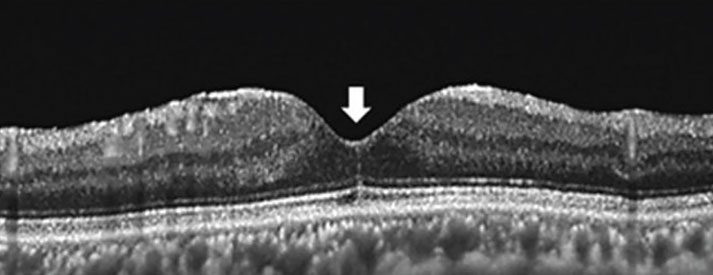

FCS (Figure 4) appears on OCT as a vertical, hyperreflective line in the foveola.6 Clinicians should be aware of this sign because it’s uniquely associated with macular hole formation following PPV for rhegmatogenous retinal detachment. Specifically, Tomoyuki Ishibashi, MD, and colleagues in Japan observed FCS in 100 percent of eyes that developed a secondary macular hole following PPV for RRD.6

They observed FCS on OCT at 255 ± 217 days following PPV, and macular hole development at 232 ± 171 days following FCS appearance, indicating that these patients should be followed longer term following RD repair.

![]() |

|

Figure 4. Foveal crack sign manifests as a vertical, hyperreflective line in the foveola (arrow). (From: Ishibashi T, Iwama Y, Nakashima H, Ikeda T, Emi K. Foveal crack sign: An OCT sign preceding macular hole after vitrectomy for rhegmatogenous retinal detachment. Am J Ophthalmol. 2020;218:192-198. Used with permission.) |